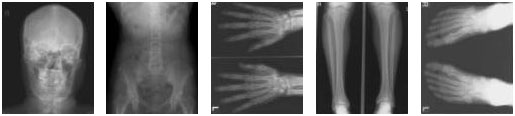

X線を頭部(骨)や腹部などにあてることで、骨折や腹部の状態を観察する検査です。造影剤を使わず、そのままの状態で撮影します。

検査の様子